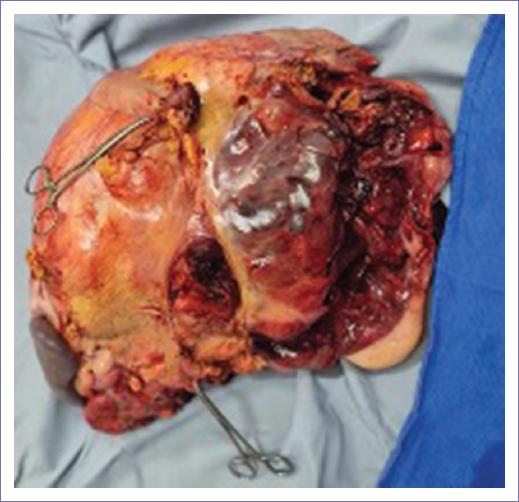

Bajo anestesia general equilibrada se procede a realizar incisión supra-infraumbilical línea media, diéresis por planos hasta cavidad abdominal, obteniendo abundante líquido peritoneal. Se encuentra tumoración adherida a peritoneo parietal y visceral de estructuras adyacentes (Fig. 3), disección roma de estructuras vasculares aorta, cava, mesentérica superior de la tumoración (Fig. 4), sin lesión de estas, obteniendo pieza quirúrgica de 40 x 40 x 25 cm, 10 kg aproximadamente, incluyendo bazo, cuerpo y cola de páncreas, hemicolon y riñón izquierdo (Figs. 5 y 6), confección de colostomía de transverso y yeyunostomía de Witzel. Se coloca penrose abocado a hueco pélvico.

Se considera como diagnóstico diferencial debido al tamaño y rapidez del crecimiento manifestado en la paciente, el tumor renal como primario, en relación con la imagen emitida en la TC, siendo este el órgano mayormente involucrado. El reporte final de estudio histopatológico de la pieza quirúrgica indica liposarcoma bien diferenciado, por lo que el pronóstico se espera bueno en función tanto de la estirpe histopatológica como de la resección completa del tumor.